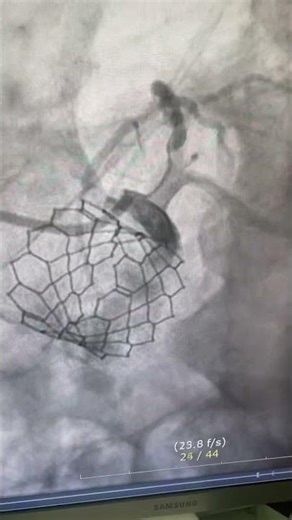

This is pci balloon 🎈 motivational video cardiovascular system anat

…

已浏览 1270 次

3 个月之前

YouTube